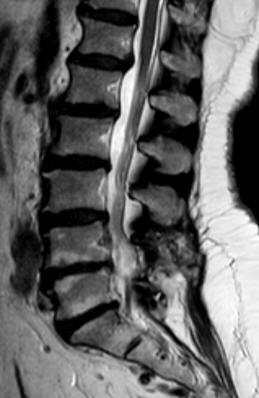

20-SEPTEMBER-2016  NAWAL ABDEL-GHAFAR ABU-SHKHEYDEM  59 YEARS  EXTRUDED DISK L3-4 WITH LEFT DOWNWARD MIGRATION.

The patient came was operated by me 03-November-2013 for extruded disk L4-5 with right downward migration. The patient was doing well until she came to the clinic 19-September-2016 telling that the last 2 months got LBP with left sciatica. MRI lumbar spine performed 07-September-2016 showing extruded disk L3-4 with left downward migration.

The extruded disk L3-4 with left downward migration in axial and sagittal views.